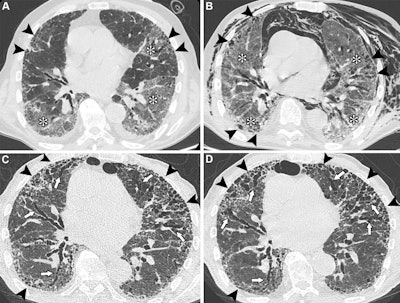

Unenhanced axial CT images show COVID-19 pneumonia in an 83-year-old male patient with preexisting interstitial lung disease (ILD). (A) Image shows ground-glass opacities in the lower lobes and in the lingula (*). Irregular reticular opacities with mild distal traction bronchiectasis are evident in the subpleural regions of both upper lobes (arrowheads), suggesting preexisting ILD with a probable usual interstitial pneumonia pattern. (B) Image obtained during hospitalization for respiratory distress shows spontaneous pneumomediastinum and diffuse chest wall subcutaneous emphysema, predominantly on the left side. The image also shows persistent, diffuse ground-glass opacities (*) and peripheral fibrotic lung changes (arrowheads). (C) Unenhanced follow-up image obtained at six months shows the progressive nature of lung fibrosis, with the development of honeycombing (arrowheads) and severe bronchiectasis (arrows), predominantly affecting the anterior peripheral regions of both lungs. (D) Unenhanced follow-up image obtained at 14 months shows the progression of honeycombing (arrowheads) and severe bronchiectasis (arrows) at the anterior peripheral regions of both lungs. In this case, SARS-CoV-2 infection likely acted as a trigger for the exacerbation of previously undiagnosed fibrotic ILD, with mechanical ventilation potentially contributing to extensive fibrosis in the anterior lung regions (arrowheads). The patient was administered antifibrotic therapy after the resolution of the acute phase.Unenhanced axial CT images show COVID-19 pneumonia in an 83-year-old male patient with preexisting interstitial lung disease (ILD). (A) Image shows ground-glass opacities in the lower lobes and in the lingula (*). Irregular reticular opacities with mild distal traction bronchiectasis are evident in the subpleural regions of both upper lobes (arrowheads), suggesting preexisting ILD with a probable usual interstitial pneumonia pattern. (B) Image obtained during hospitalization for respiratory distress shows spontaneous pneumomediastinum and diffuse chest wall subcutaneous emphysema, predominantly on the left side. The image also shows persistent, diffuse ground-glass opacities (*) and peripheral fibrotic lung changes (arrowheads). (C) Unenhanced follow-up image obtained at six months shows the progressive nature of lung fibrosis, with the development of honeycombing (arrowheads) and severe bronchiectasis (arrows), predominantly affecting the anterior peripheral regions of both lungs. (D) Unenhanced follow-up image obtained at 14 months shows the progression of honeycombing (arrowheads) and severe bronchiectasis (arrows) at the anterior peripheral regions of both lungs. In this case, SARS-CoV-2 infection likely acted as a trigger for the exacerbation of previously undiagnosed fibrotic ILD, with mechanical ventilation potentially contributing to extensive fibrosis in the anterior lung regions (arrowheads). The patient was administered antifibrotic therapy after the resolution of the acute phase.RSNA